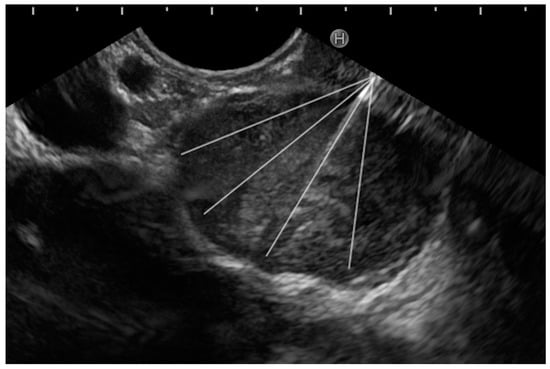

- Fanning technique: This technique entails the initiation of the biopsy from the left margin of the tumor mass, and the needle is “fanned” till the right margin is reached. The trajectory of the needle is altered using the up–down knob or the elevator. In this fashion, the needle is positioned at four different areas within the lesion, and four actuations are performed in each area (Figure 5). This is termed as the ‘4 × 4’ rule’.